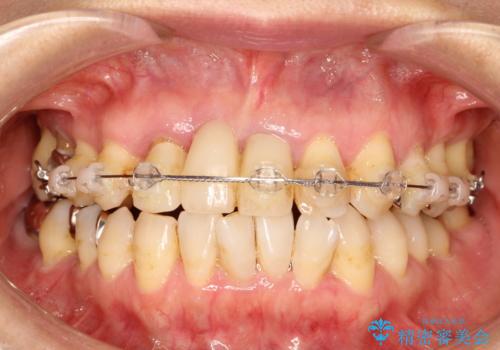

矯正を併用した前歯のセラミックブリッジ治療

- 上顎前歯をきれいにしたいとのことで来院されました。

レントゲンを撮影すると保存が難しい歯がありました。

またがたつきの度合いから歯を1本抜歯して矯正治療を行いセラミックブリッジを装着することで、審美的・機能的改善を行う計画としました。

治療の順序は

①保存不可の歯の抜歯・根管治療

②矯正治療

③セラミックの装着

という流れで行いました。

1年程度の治療期間が必要となりましたが、仕上がりには患者様に満足していただけました。